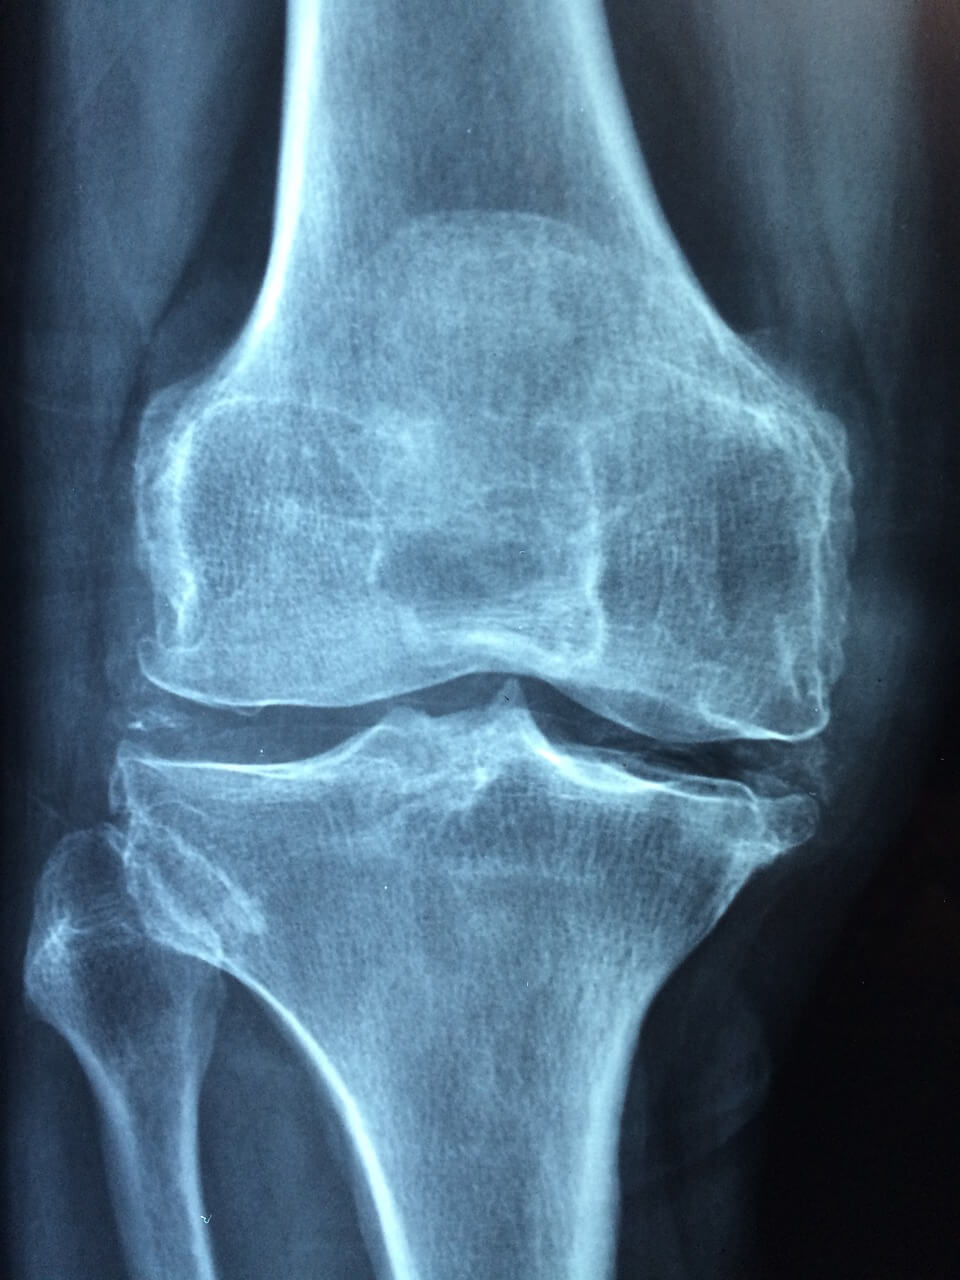

혹시 관절 영양에 문제가 생기셨나요? 40대부터 60대까지 관절 통증은 성인병으로 보통 관절 영양제를 먹는 것으로 건강을 개선하고자 합니다. 어떤 성분이 관절 영양제에 들어가면 좋은지 추천을 받아보시고 언제 먹으면 좋은지 먹는 시간까지 함께 관절 영양 개선에 대한 정보를 얻어가시기 바랍니다.

관절 건강을 지원하는 영양제는 다양하게 시장에 나와 있습니다. 그 중에서도 글루코사민과 콘드로이틴은 관절 연골의 건강을 보호하고 염증을 줄이는 데 도움을 줄 수 있습니다. 또한 오메가-3 지방산은 관절 염증을 감소시키고 유연성을 증진시키는 데 도움이 됩니다. 관절 영양은 평소에 관리하는 것이 중요하며, 나이가 들수록 쉽게 회복되기 어려운 관절과 관련된 사안은 반드시 가볍게 여기지 않아야 합니다.

관절 영양제 추천 30대가 넘는 성인이거나 60대가 넘으셨다면 관절 영양제 복용을 통해 얼마든지 건강한 관절을 유지하며 삶을 즐기실 수 있습니다. 더불어 올바른 식습관과 꾸준한 운동, 적절한 관절 영양제 복용은 풍요로운 노후를 위한 중요한 요소입니다. 지금 관절 상태를 점검해보시고, 관절 가동성 또는 통증 등 문제가 있다면 지체없이 가까운 병원을 내방하셔서 상담받아보시기 바랍니다.